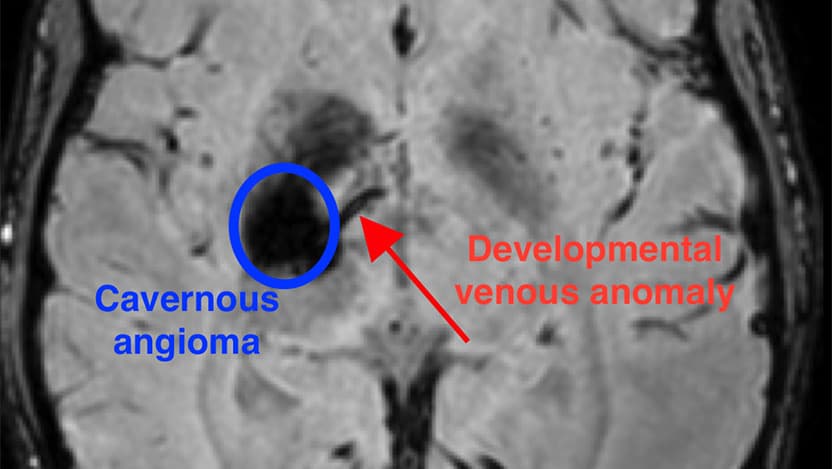

The new research has identified a unique combination of mutations that occurs during the development of the brain that results in a cavernous angioma. First, a mutation in the gene PIK3CA leads to an abnormal pattern of vessels in the brain, known as a developmental venous anomaly, or DVA. The DVA alone is generally innocuous. But when a second mutation in one of several genes, such as MAP3K3, KRIT1, CCM2, or PDCD10, occurs in the area of the abnormal vein, a cavernous angioma develops.

“We’d previously observed that often these lesions grow near a preexisting abnormal vein,” said Awad. “But these DVAs are actually very common – about 6% to 10% of people have one, and the vast majority of them never have any problems. Rarely, those veins grow a cavernous angioma and we’ve never known why. In this study, we were finally able to use mutation analysis on the vein itself, to see why the vein seems predisposed to these angiomas.”

“This is very novel, because we can now explain why the DVA forms in the first place,” said Awad. “Along with a second mutation, it is the genetic seed for the formation and growth of the cavernous angioma.”